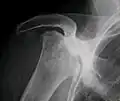

La mayoría de las veces los doctores ortopédicos diagnostican la enfermedad excepto en la mandíbula, donde normalmente es diagnosticado y tratado por cirujanos dentales y maxilofaciales. El examen de elección es la resonancia magnética, capaz de detectar osteonecrosis antes de que haya daño significativo en el hueso.

La osteonecrosis es más común en la articulación de la cadera. Se utilizan varios métodos para tratar la enfermedad,.[11]​ El más común es del reemplazo total de la cadera, por un implante protésico. Sin embargo, esto conlleva problemas que incluyen tiempos de recuperación largos y menores esperanzas de vida. Este es un método efectivo para la población geriátrica; sin embargo, los médicos evitan usarlo en pacientes jóvenes por las razones mencionadas. Existe un tratamiento más nuevo y prometedor con un metal, en el que no se elimina todo el hueso, sino que se repara. En este, sólo se retira la cabeza del fémur, a diferencia del reemplazo completo donde se retira todo el cuello. Esta técnica aún está en estudio y experimentación.